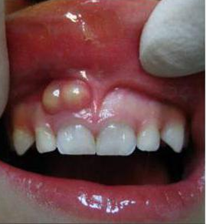

白箭头指示上颌窦牙龈瘘

2)根尖囊肿,也称神经根囊肿,由牙齿感染引起;通常见于30-60岁,主要症状是深龋洞,牙齿变色,反复出现牙龈脓包等。